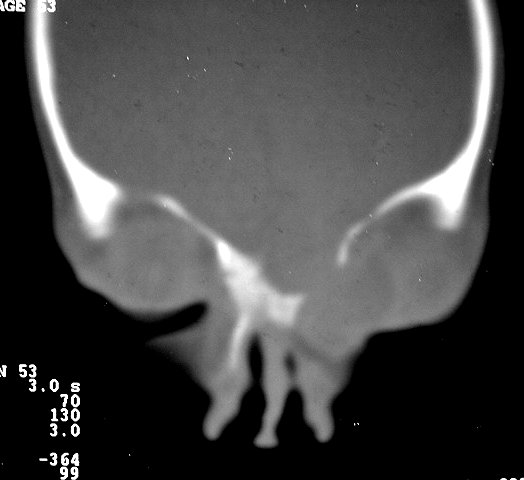

Орбитальная патология. Черепно-мозговые грыжи. +

Фронто-орбитальное энцефалоцеле